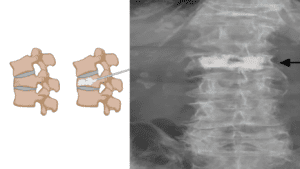

Entendendo a Diferença entre Abaulamento, Protusão e Hérnia de Disco Extrusa

Este post aborda as diferenças entre abaulamento, protusão e hérnia de disco extrusa, explicando suas características, sintomas e tratamentos. Aprenda a identificar cada condição e conheça as opções de tratamento disponíveis para aliviar a dor e...